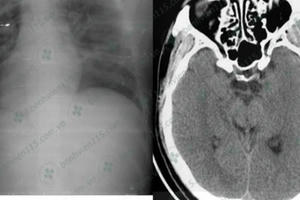

Bắc Giang: Thiếu niên bị đánh hội đồng dẫn đến hôn mê, đa chấn thương

Đi chơi tối, một thiếu niên bị nhóm đối tượng bất ngờ tấn công bằng vỏ chai bia thủy tinh dẫn đến chấn thương sọ não, hôn mê sâu.

Một nam thanh niên 35 tuổi sau nhiều năm nghiện món tiết canh đã nhập viện trong tình trạng hôn mê, phải mổ cấp cứu do bị sán “ăn” não.